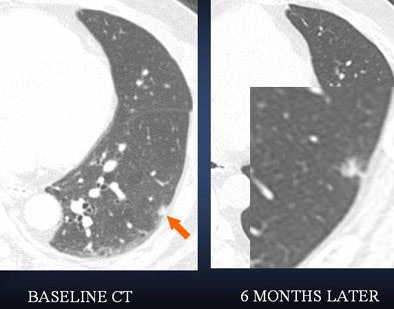

| In a 61-year-old woman a 6-mm nodule was found in the right lower lobe at baseline CT scan. At six-month follow-up, the nodule was determined to be stable in size. At 12 months, however, it had clearly grown in size. The nodule was biopsied and eventually diagnosed as adenocarcinoma. All images courtesy of Dr. Ann Leung. |

"If you look at the 12-month study (61-year-old woman, above), you will appreciate air lucency within that nodule," Leung said. "We're recognizing now as we are scrutinizing nodules much more carefully that the presence of air bronchograms is a concern for malignancy," she said. "If we look back at the first image, at six months, we can see that this lesion also had air bronchogram. We should have been more aggressive in trying to provide a diagnosis for this patient."